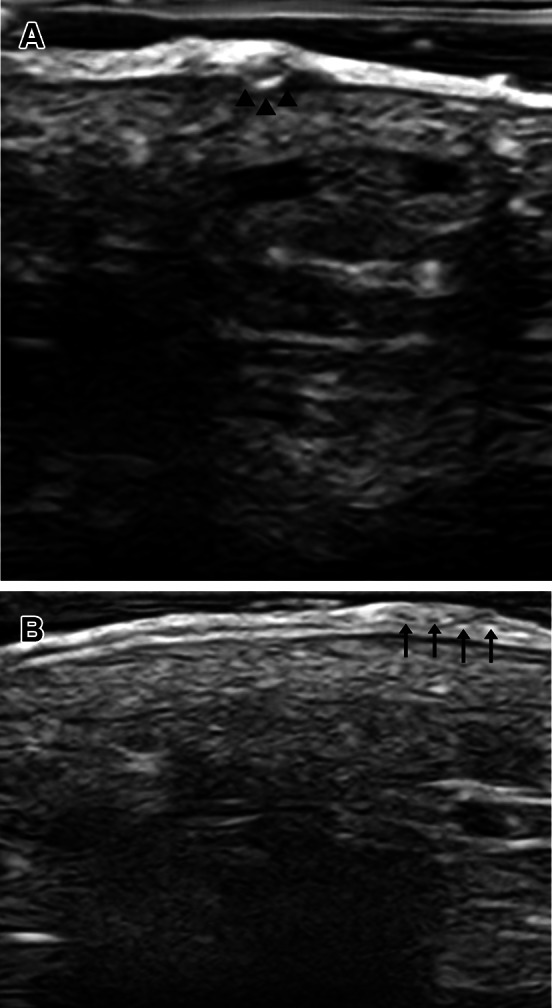

We could observe in the site with the “triangle” sign a hyperechoic well-defined ovoid area within the epidermal layer (Fig. 2A). The burrow showed an image of tiny heteroechoic dots within the epidermis that, we could hypothesize, were the eggs laid by the mite (Fig. 2B).

Fig. 2.

Greyscale US exam. A Hyperechoic well-defined ovoid area (marked with arrows) within the epidermal layer at the site where the “triangle” sign is present. B Tiny heteroechoic dots within epidermis